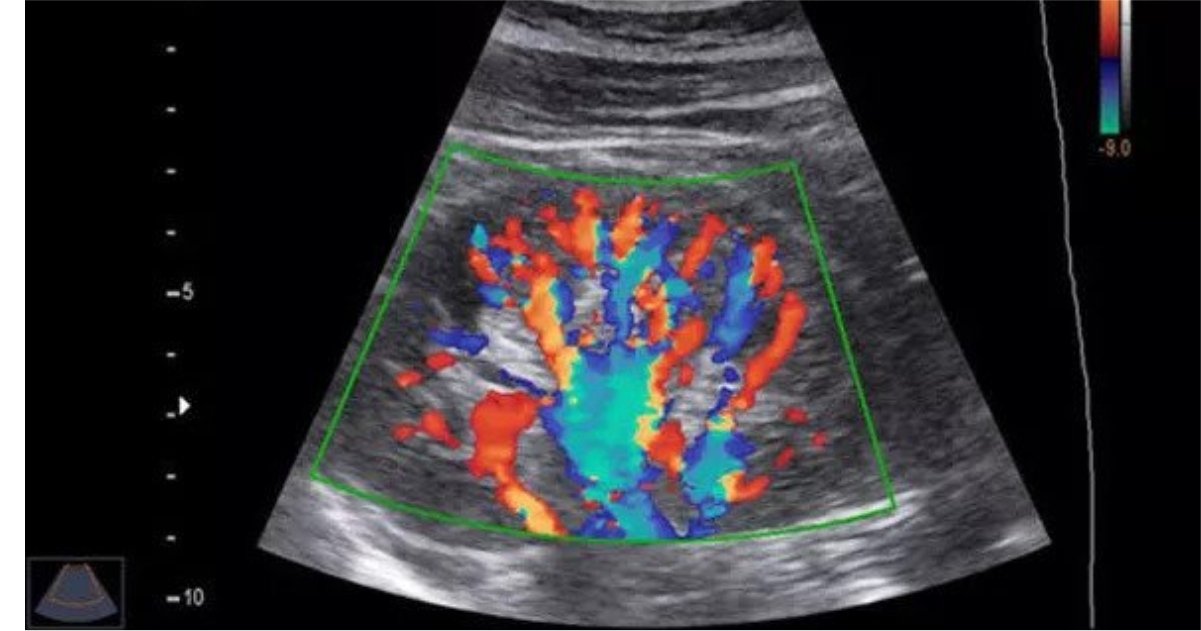

Color Doppler

Our Color Doppler studies provide detailed evaluation of blood flow through arteries and veins, helping detect vascular abnormalities early.